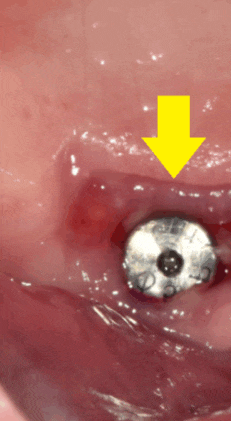

잇몸을 보면 이런 모습입니다!!

230531

엑스레이를 보면 이런 형태입니다.

임플란트 위에 작은 나사가 올라가있죠?

이게 힐링이에요